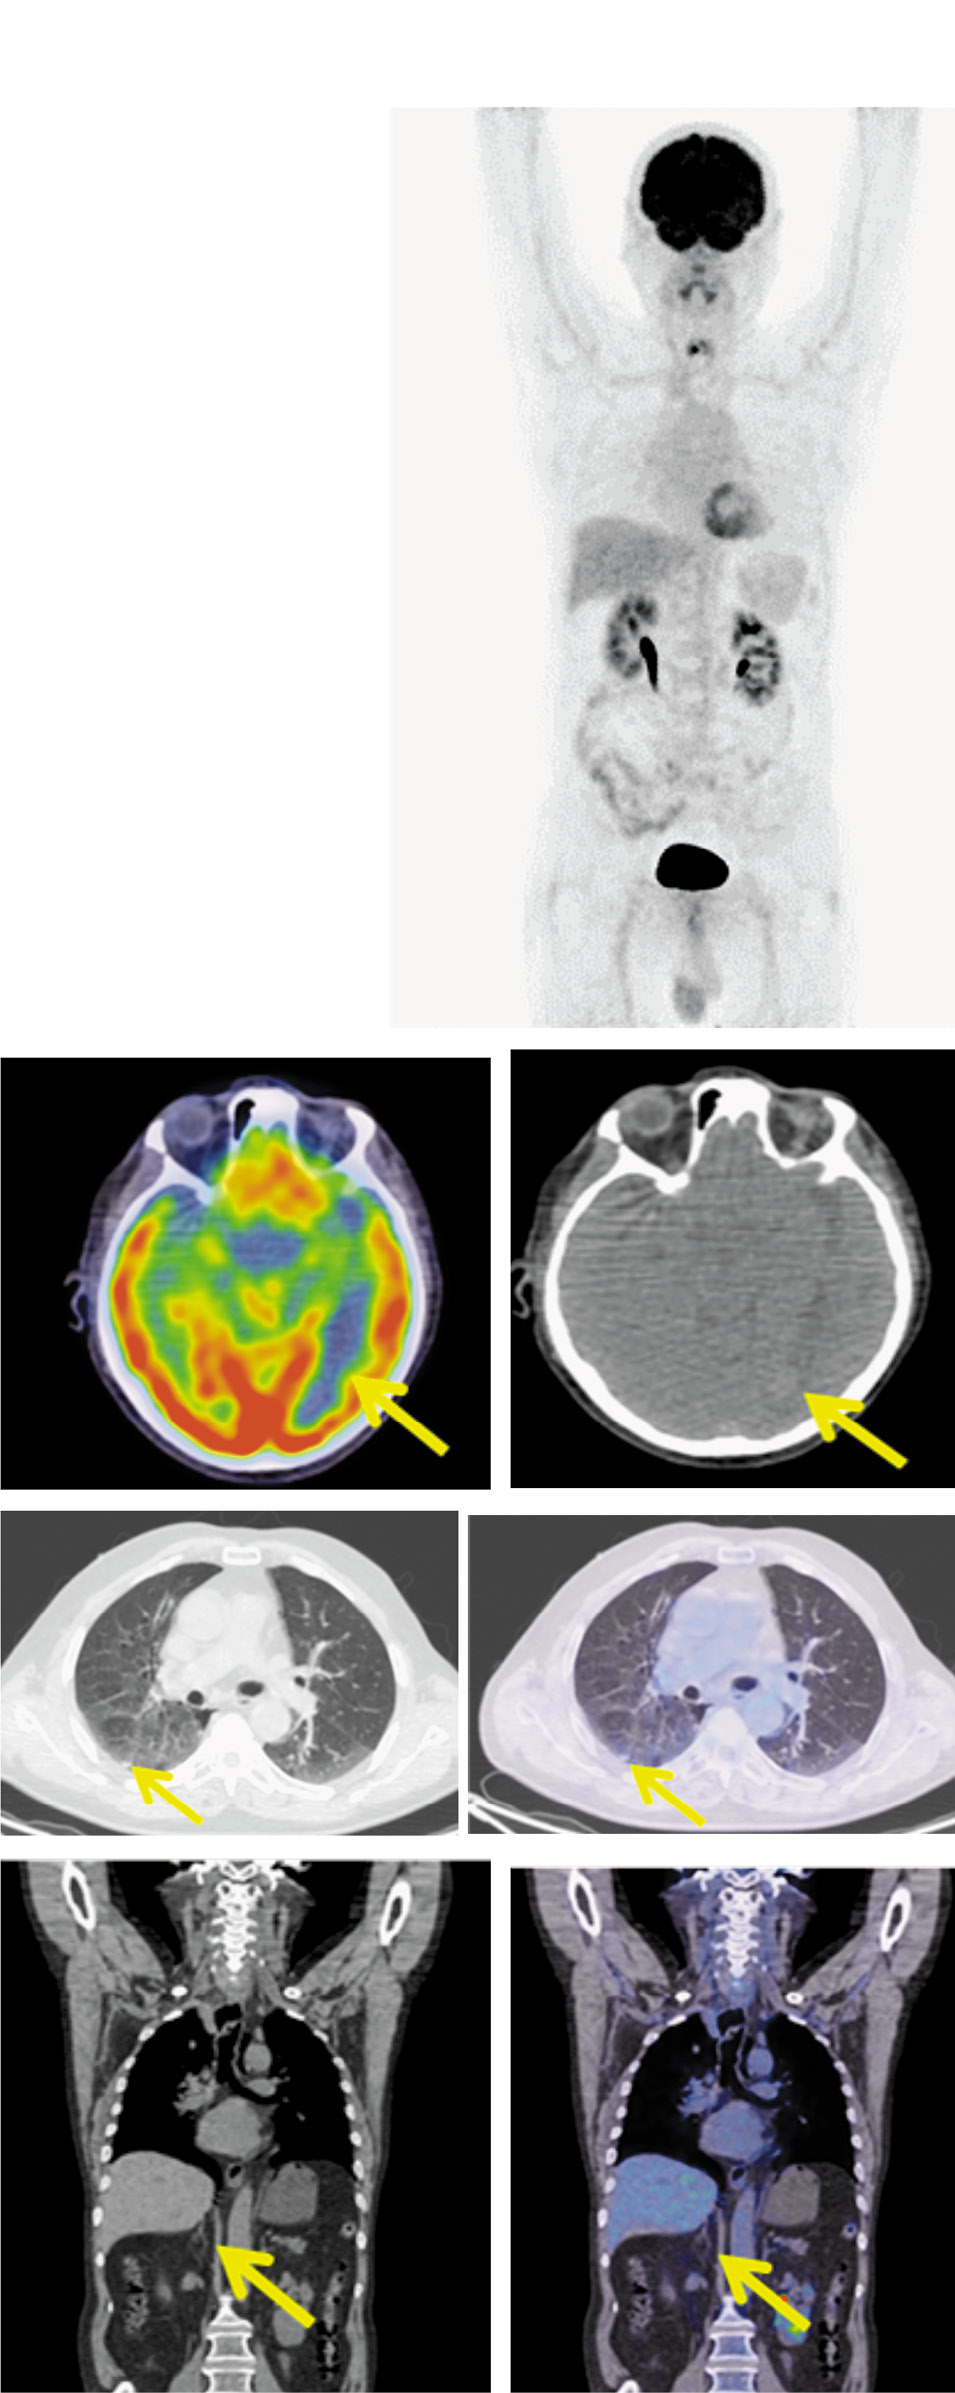

Рис. 7. Пациент Н.,64 года, после 40-го цикла терапии. На MIP, аксиальной и корональной КТ и ПЭТ/КТ проекциях в левой затылочной доле – без фиксации РФП. Лимфатические узлы шеи не увеличены и метаболически не активны. В субплевральном отделе S6 правого легкого – образование без динамики до 9×6 мм, без метаболической активности ФДГ. В задневерхнем средостении паратрахеально справа сохраняется уплотнение клетчатки без четких контуров и очаговой фиксации РФП. Медиастинальные лимфатические узлы не увеличены. Опухоли в правом надпочечнике нет.

Fig. 7. A 64-year-old patient N. The condition of the patient after 40 cycles of therapy. MIP, axial and coronal images show the left occipital lobe without increased uptake of radiopharmaceutical. Cervical lymph nodes are not enlarged and without metabolic activity. In the subpleural section of the right lung S6 segment the lesion is the same, measuring 9×6 mm, without increased RFP uptake. In the posterosuperior mediastinum in the right paratracheal space, fiber compaction with poorly defined boundaries is still detected and without focal increased radiopharmaceutical uptake. Mediastinal lymph nodes are not enlarged. There is no tumor in the right adrenal gland.

По данным МРТ головного мозга через 26 мес – без отрицательной динамики, очаговой патологии не выявлено. Лечение атезолизумабом в дозе 1200 мг продолжено. Нежелательных явлений не отмечалось. После 40-го цикла осуществлена оценка эффективности лечения. По данным ПЭТ/КТ от 02.09.2021 с 18-ФДГ в левой затылочной доле – без фиксации РФП. Лимфатические узлы шеи не увеличены и метаболически не активны. В субплевральном отделе S6 правого легкого – образование без динамики, до 9×6 мм, контактирующее с костальной плеврой, без метаболической активности ФДГ. В задневерхнем средостении паратрахеально справа сохраняется уплотнение клетчатки без четких контуров, сливающееся с правой стенкой пищевода без очаговой фиксации РФП. Медиастинальные лимфатические узлы не увеличены. Образование в правом надпочечнике регрессировало (рис. 7). По критериям RECIST v.1.1 полученная ранее полная метаболическая регрессия сохраняется.